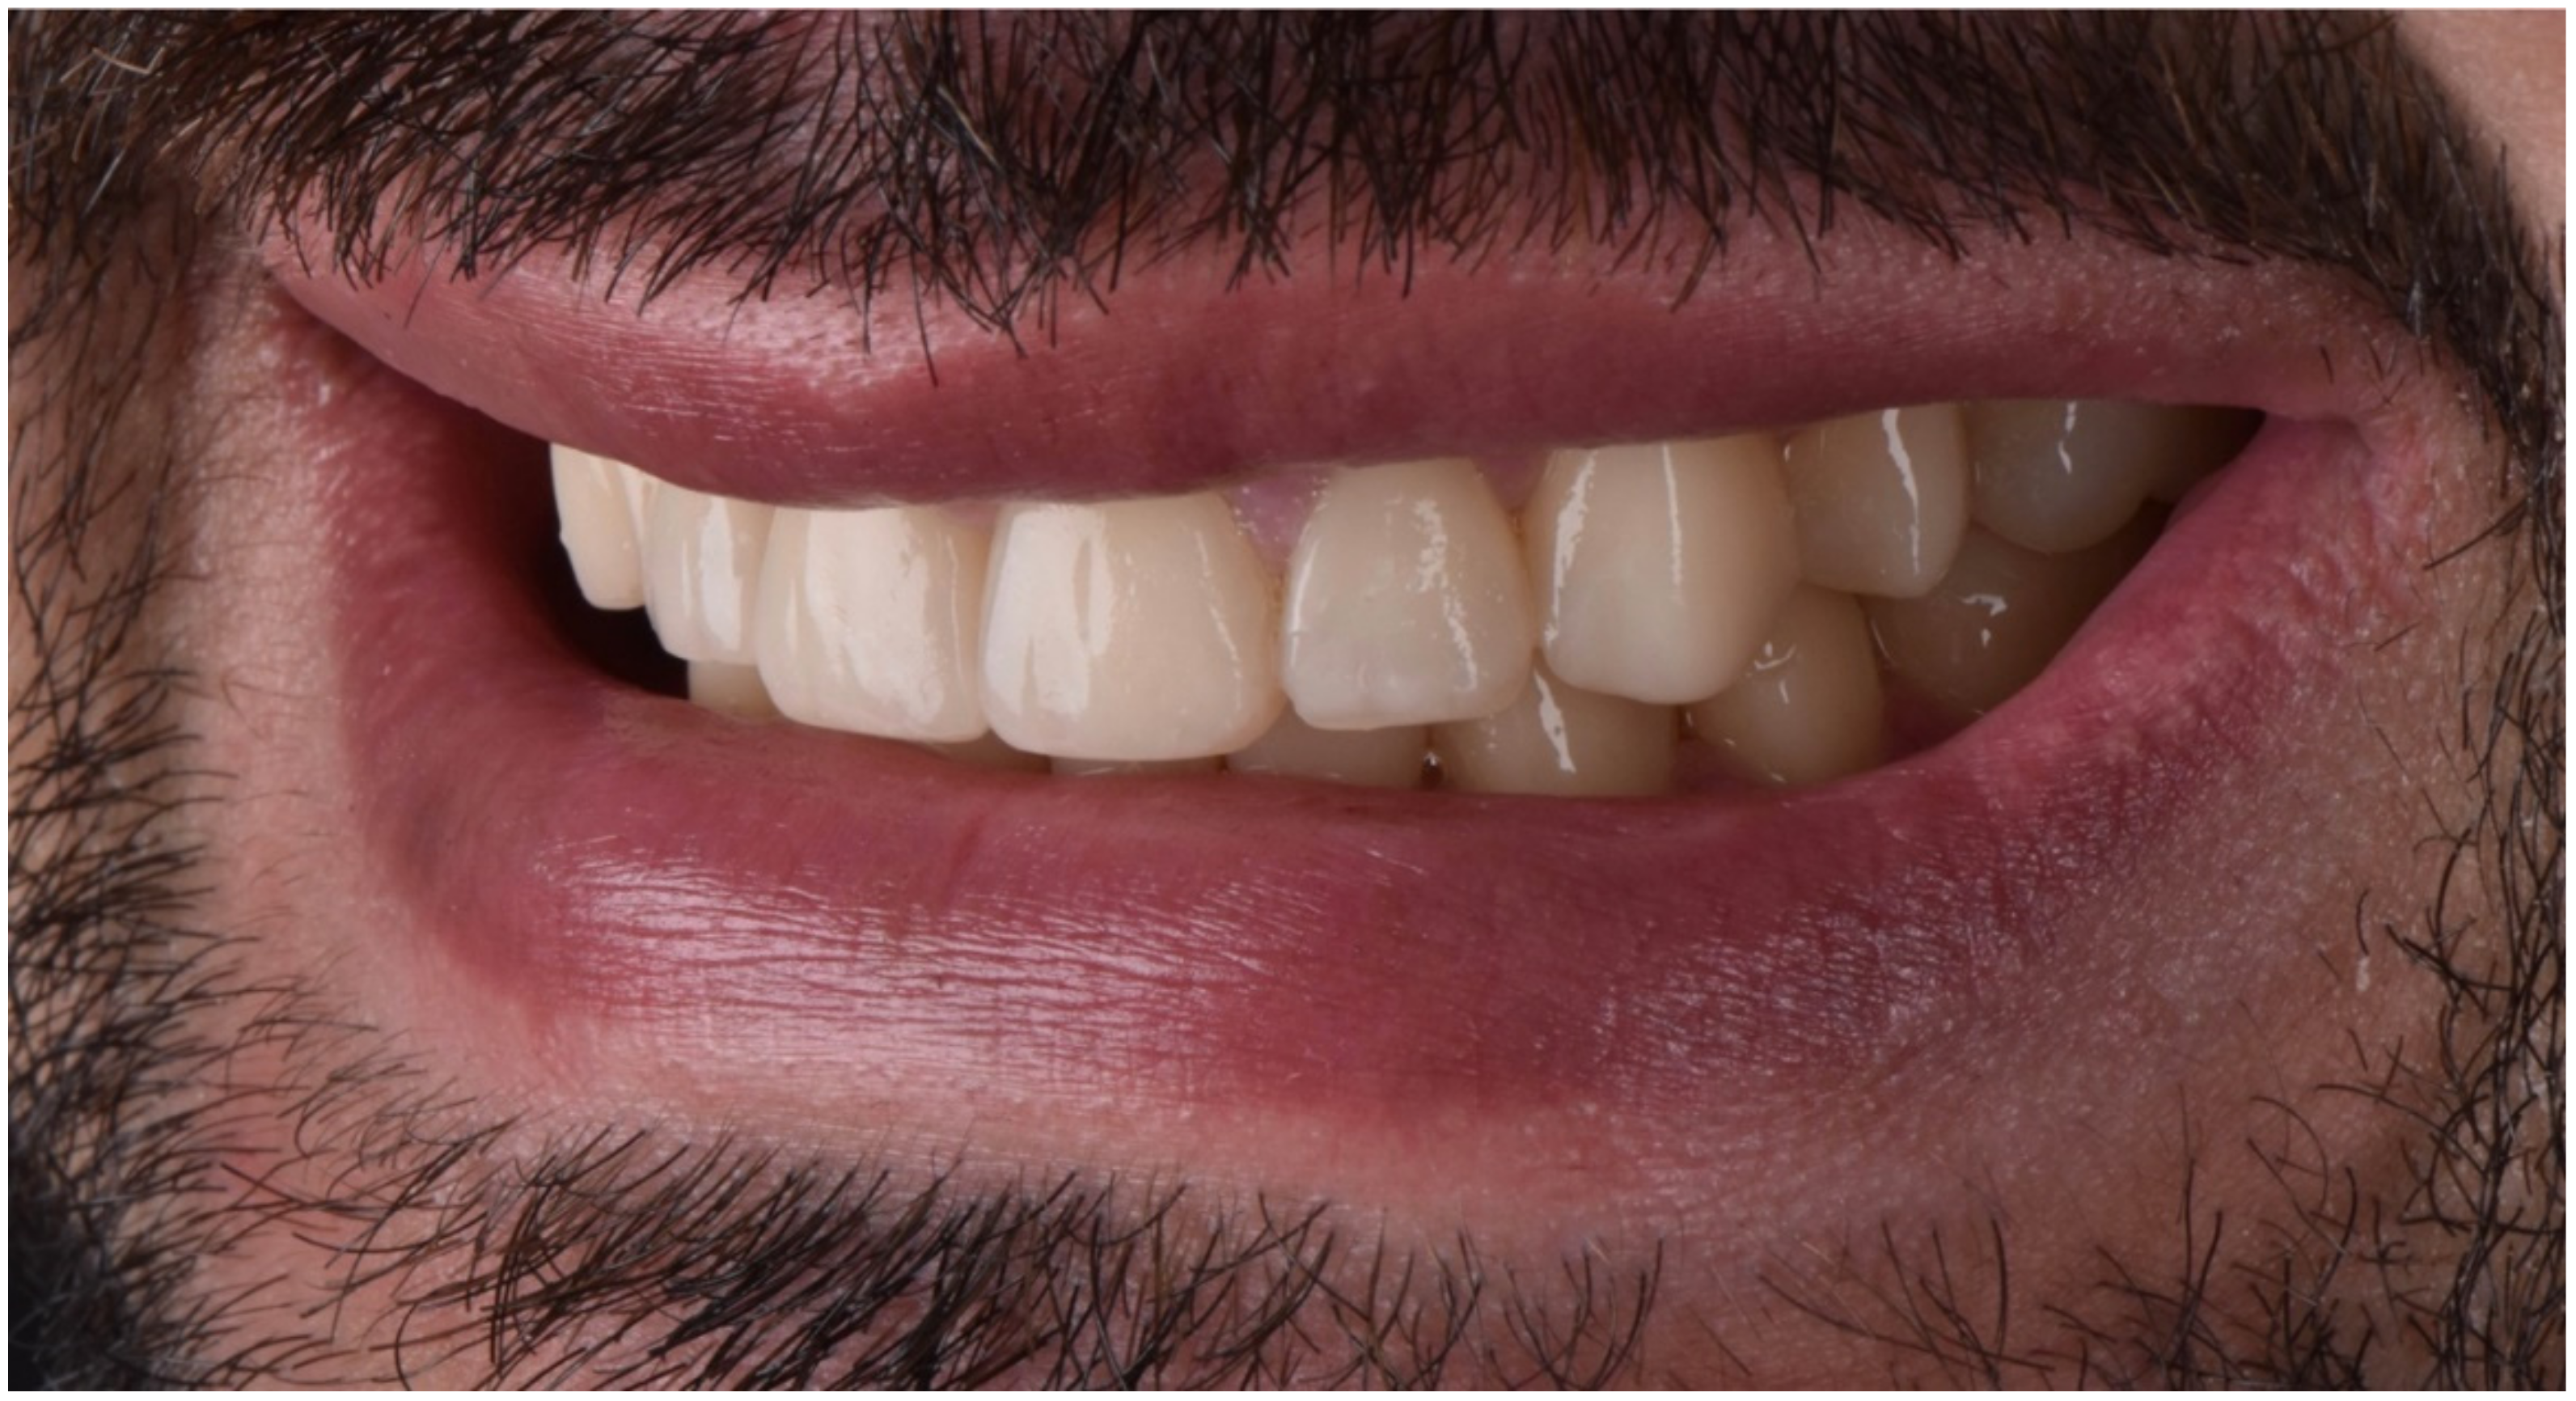

2.2. Restorative Phase